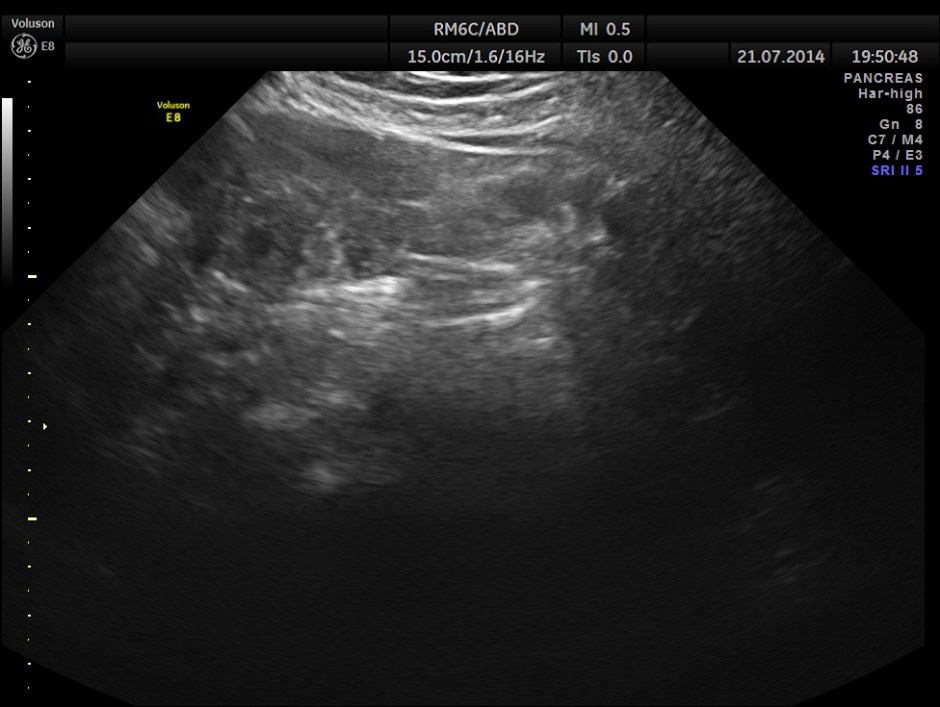

The following pictures show the pancreas.

Pancreatic duct is dilated prominently.

Pancreatic duct dilated.- 12.9 mms.

Pancreatic calculi are seen.